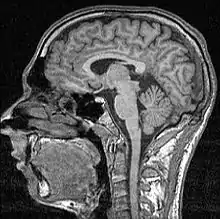

Date din neurobiologie

Imaginile neuronale drept dovezi susțin efectul de bucurie a dăruirii. Investigările recente cu utilizarea imagisticii prin rezonanță magnetică funcțională a subiecților care iau decizii de a dona, identifică zona subgenuală și striatul ventral drept regiuni asociate cu dăruirea socială. [59] Recompensele mezolimbice ale dăruirii sunt similare neurobiologic cu primirea de recompense materiale. [4] Consensul general în domeniul psihologiei și a neurobiologiei este acela că ajutându-i pe alții, oamenii devin fericiți prin eliberarea de oxitocină și endorfine. [16]